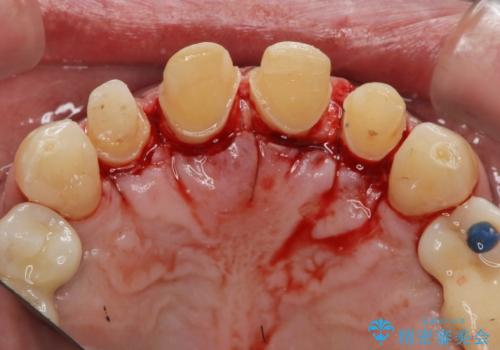

「 放置した虫歯 」 前歯セラミック治療

- 前歯の虫歯に気付きながらも放置し、一念発起し治療を希望され来院されました。

虫歯のマイクロスコープによる丁寧な除去、根管治療、深い虫歯に対する挺出(エクストリュージョン)および歯周外科を行ったのち精度の高いセラミッククラウン製作治療を計画します。

虫歯の放置により、根管治療や深い虫歯に対する処置が必要になりましたが丁寧に一つづつ処置を行ったことで抜歯をすることなく歯を残すことができました。

セラミッククラウンの製作をする前に、歯内・歯周環境の整備は非常に大切です。